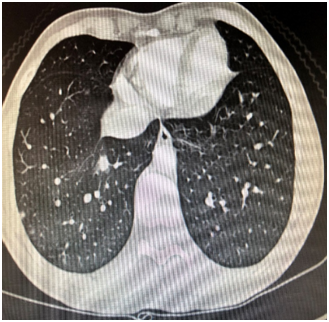

A 30 year old woman was admitted for dry cough, polyarthralgia, and subfebrile fever that developed following two weeks of amoxicillin-clavulanate treatment for maxillary sinusitis. Her past medical history was remarkable. The family history did not reveal any disease of medical interest. Four weeks before admission the patient developed fever (38.4°C), postnasal purulent discharge, and maxillary pain. WBC was 13.2×103/ml with 79 percent neutrophils, CRP: 55.5, ERS: 48mm/h. The patient was commenced on amoxicillin clavulanate 1000mg bid for fourteen days. Dry cough, dyspnea on exertion, polyarthralgia, and fever occured three weeks after amoxicillin clavulanate treatment. Chest x-ray was normal (Figure 1). Blood biochemistry was within normal limits. There was no radiologic abnormalitiy on joint films. Arterial blood gases; pH: 7.39, pO2: 84.2, and pCO2: 38.6mm Hg. ECG revealed sinus rhytm (84/min). Tuberculin test was negative. Chest CT showed bilateral multiple subpleural nodules in the lingula (one; 3mm), left lower lobe (multiple; 1-2mm), right lobe anterior segment (two; 5mm and 15X10mm) (Figure 2). Serum ACE was 24U/L. Sputum smear and culture were negative for bacteria, mycobacteria, and fungus.

Figure 2 Chest CT revealing pulmonary nodules.

It has long been known that many drugs, including antibiotics can induce DIL or vasculitis.1,3 Patients can be designated as DIL or vasculitis according to the accepted definitions, clinical, and serological findings. We present a case that presented with an atypical clinical picture of vasculitis following amoxicilline-clavunate treatment for maxillay sinusitis revealing overlapping manifestations of DIL and vasculitis5,6 due to amoxicillin-clavulanate. The final diagnosis was DIL due to positive anti-histone antibody. After steroid treatment, the patient showed an outstanding outcome with resolution of symptoms, clinical, laboratory, and radiologic findings. The patient was a diagnostic challenge for the clinician because the risk of developing DIL with amoxicillin-clavunate is extremely rare.4,6,7 Moreover, the distinction between DIL and vasculitis was not achievable due to the the significant overlap of the clinical manifestations between these two entities in our case. DIL patients present with various manifestations like arthralgia, pericarditis, pleuritis, and fever. Dry cough, subfebrile fever, and polyarthralgia were the predominant symptoms in our case. Chest CT revealed pulmonary nodules and enlarged mediastinal lymph nodes that are unusual in DIL. And thirdly, the clinical manifestations were atypical for DIL. Notably the presence of subpleural nodules and the enlarged mediastinal lymph nodes identified by chest CT lead to diagnostic confusion.